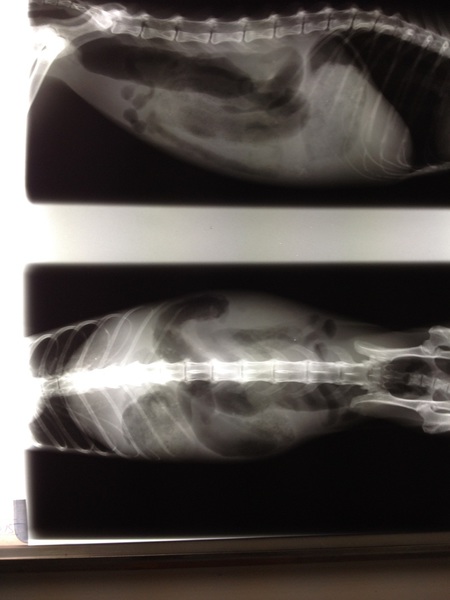

Guten Tag! Ich bin Frida und mir ging es wirklich, wirklich elend. Ich kann Euch sagen, ein Leben begleitet von ewiger Übelkeit mit Erbrechen ist irgendwann kein so schönes Leben mehr. Schliesslich landeten wir bei Doc UU. Der gab mir so weisses Zeugs (Anmerkung Autorin: Kontrastmittel) ein. Na ja, irgendwie hat's nicht so schlecht geschmeckt aber es war halt ganz schön viel. Schliesslich wurde ich geröngt und dank dieses Mittels stellte Doc UU fest, dass mein Darm voller Haare war. Ebenfalls dank dieses Mittels verliessen diese vielen Haare ENDLICH meinen Darm..... jetzt geht es mir wieder gut und die ewige Kotzerei - pardon der Ausdruck - hat Ende. Herzliche Grüsse von Frida